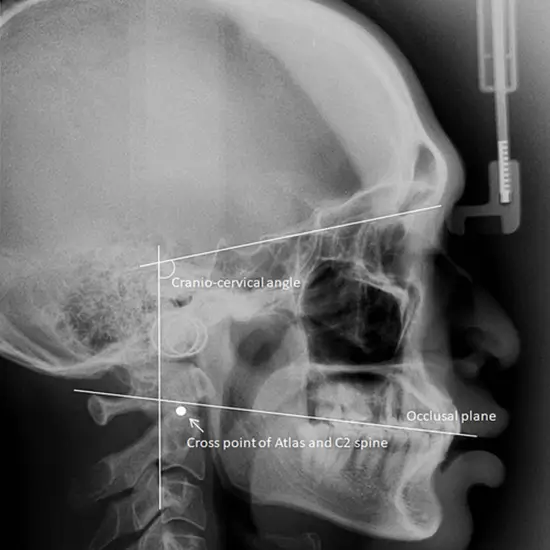

This examination uses an X-ray of the temporomandibular joints to see this joint and the surrounding soft tissues, such as skin and muscles. The temporomandibular joint (TMJ) connects the mandible (jaw bone) and the skull.